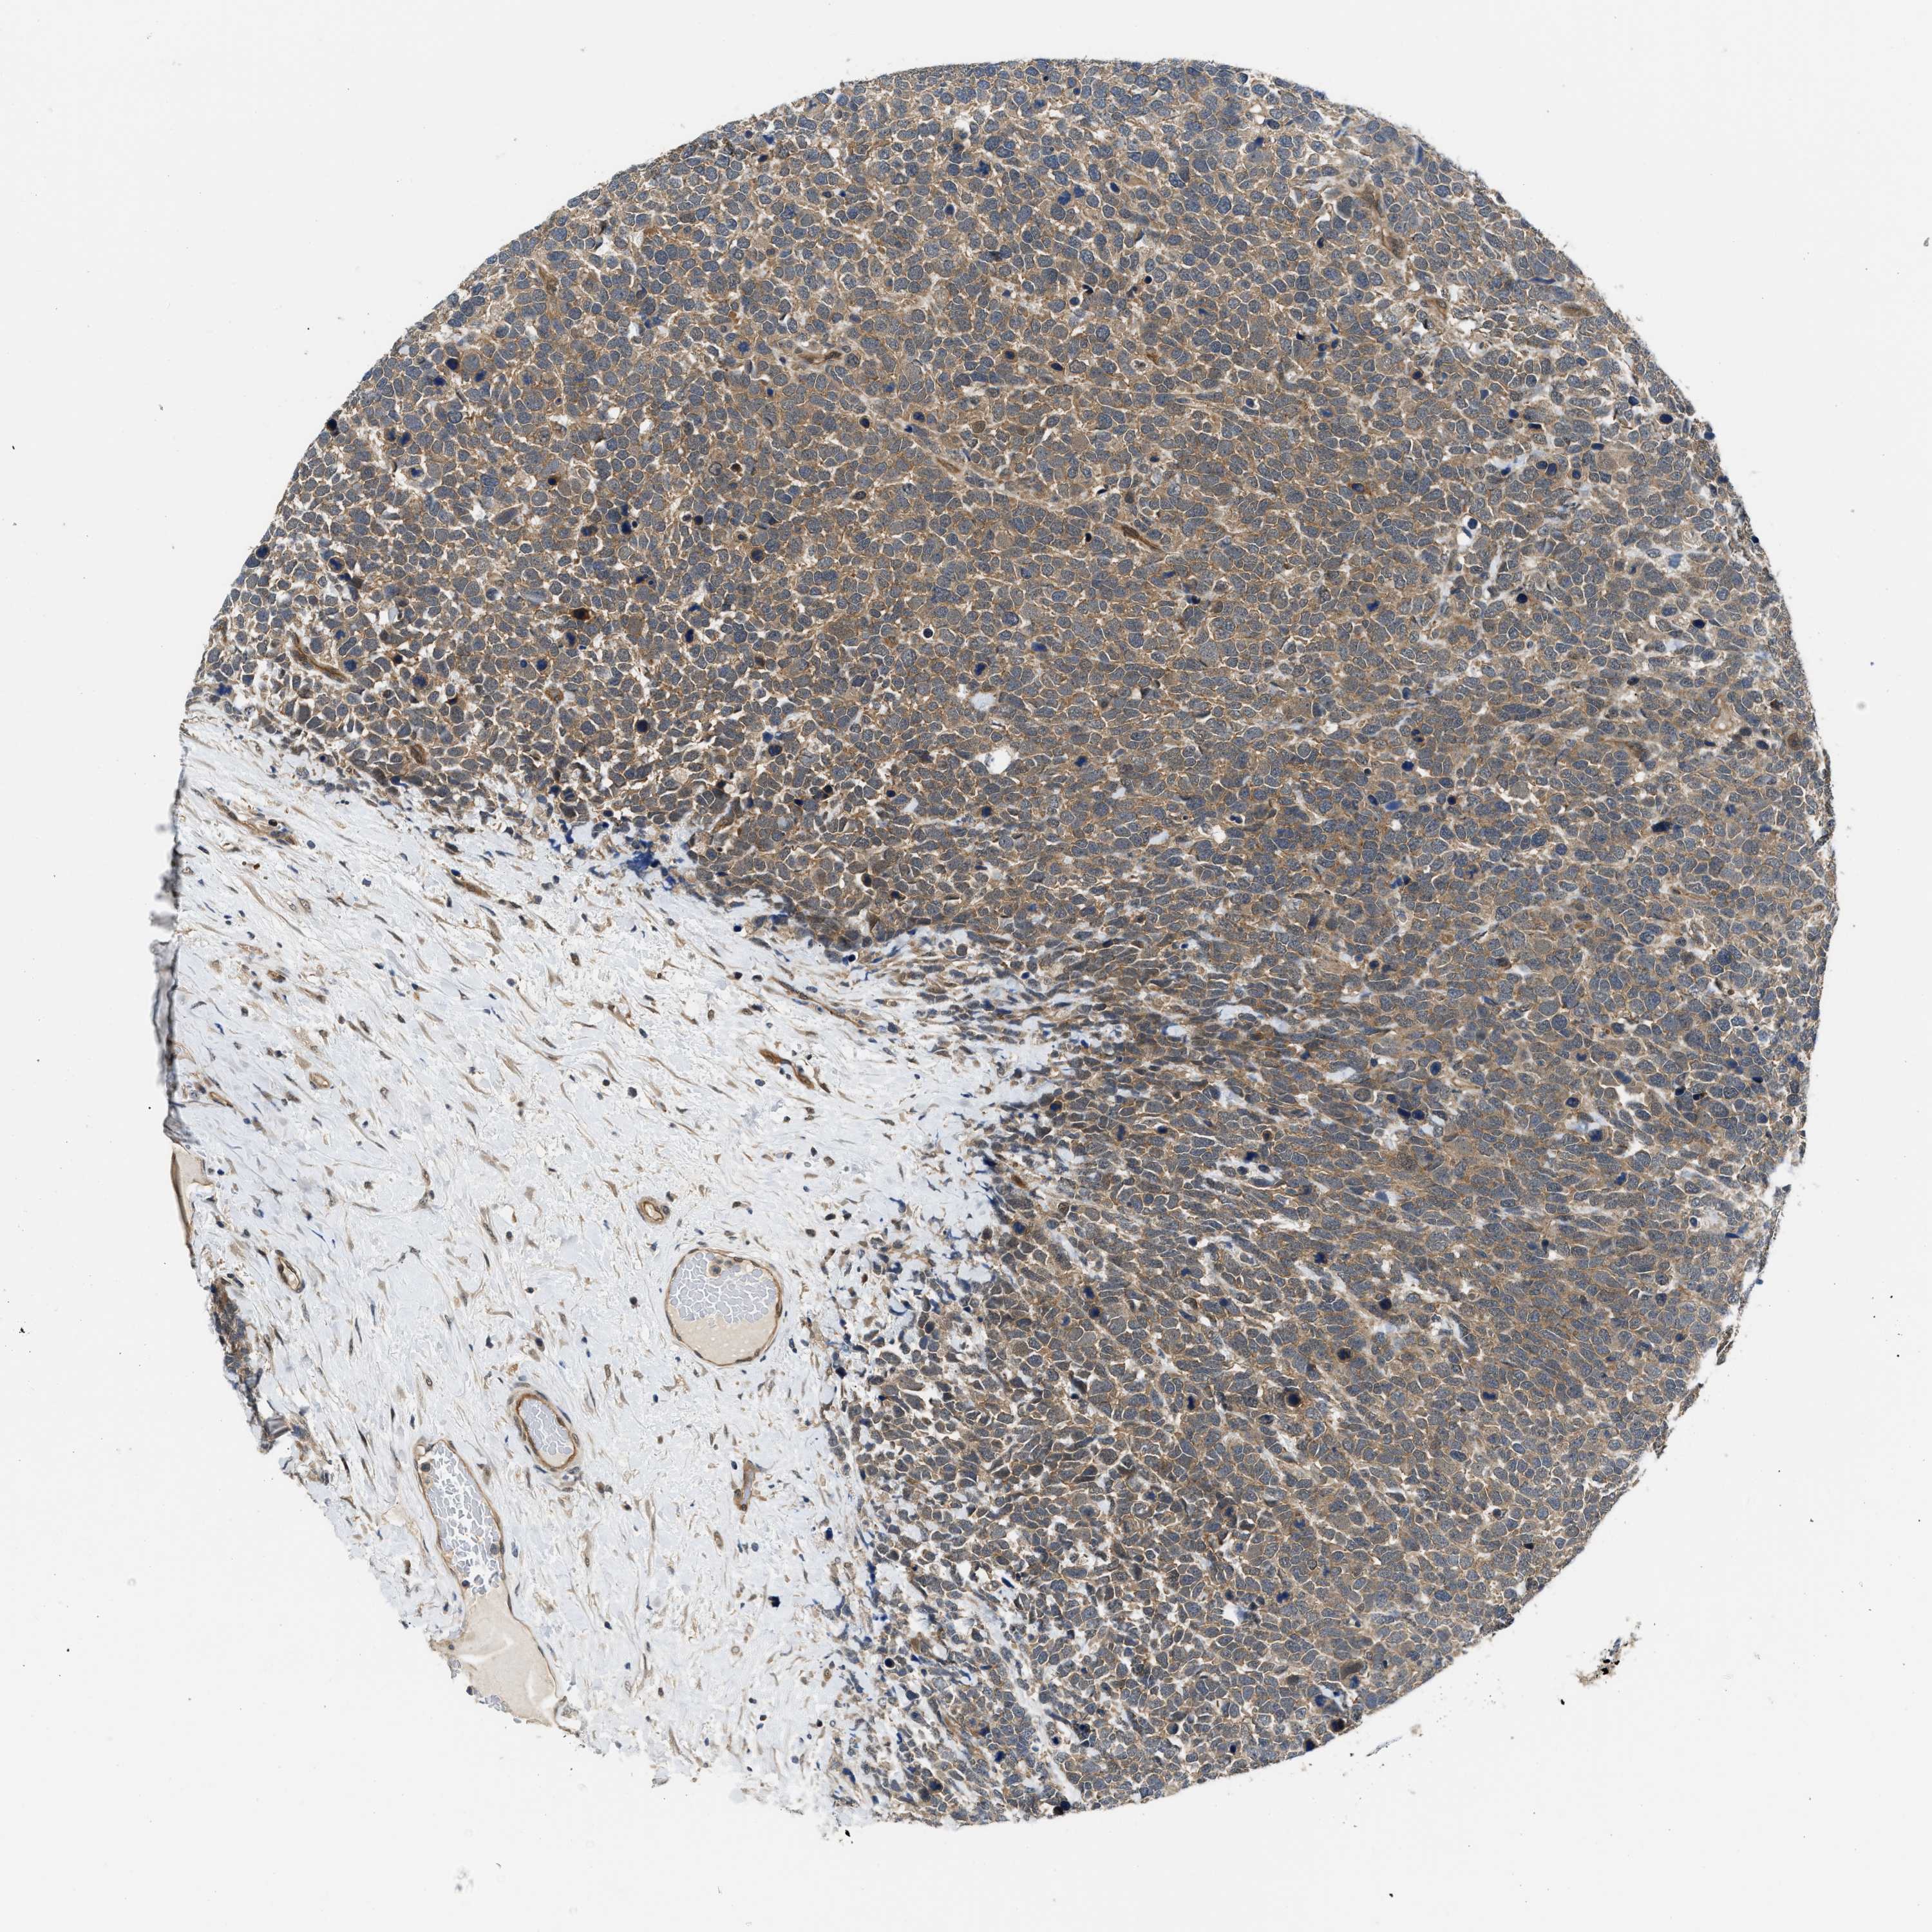

UROTHELIAL CANCER - Protein expressioni

A mouse-over function shows sample information and annotation data. Click on an image to view it in a full screen mode. Samples can be filtered based on level of antibody staining by selecting one or several of the following categories: high, medium, low and not detected. The assay and annotation is described here.

Antibody stainingi

Antibody staining in the annotated cell types in the current human tissue is reported as not detected, low, medium, or high, based on conventional immunohistochemistry profiling in selected tissues. This score is based on the combination of the staining intensity and fraction of stained cells.

Each image is clickable and will lead to virtual microscopy that enables deeper exploration of all samples and also displays staining intensity scores, fraction scores and subcellular localization as well as patient and tissue information for each sample.

Antibody HPA018271

Urothelial carcinoma, Low grade

Urothelial carcinoma, High grade